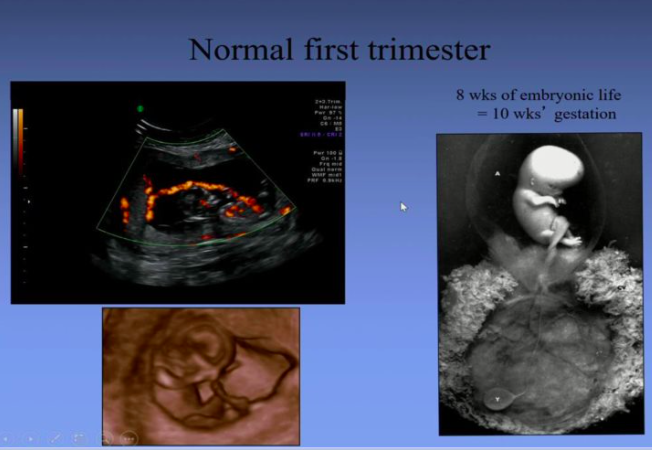

When does an embryo start to be called a fetus?

10 weeks gestation